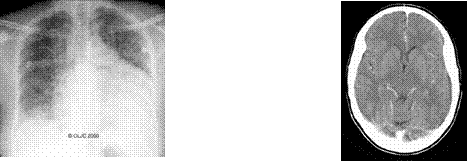

Nesta especialidade são estudados não só raios-X, mas também todas as imagens obtidas a partir de outras formas de radiação de alta energia. Estão assim

incluídos raios–X (fig. 1.1 a), tomografia assistida por computador (fig. 1.1 b), ressonância magnética, ultrassons, medicina nuclear, termografia e fluoroscopia.

Fig. 1.1 a) Raio X Fig. 1.1 b) TAC